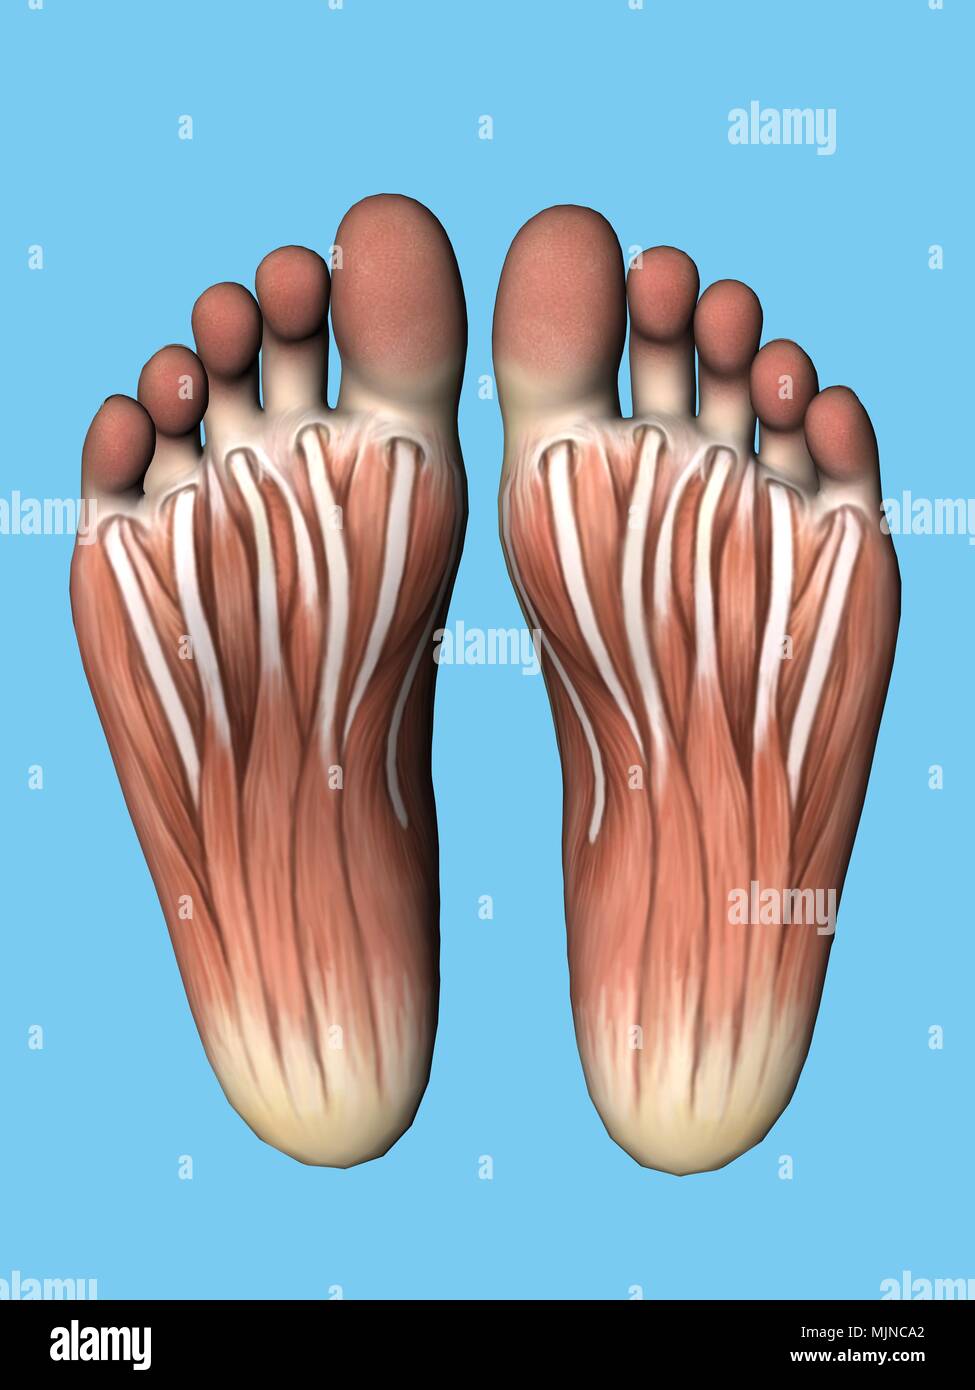

RF2ABM669–La médecine et les soins de l'illustre le tableau, les droits de l'anatomie du pied : Peau et tissus ectodermaux, os, muscles nerfs, vaisseaux sanguins